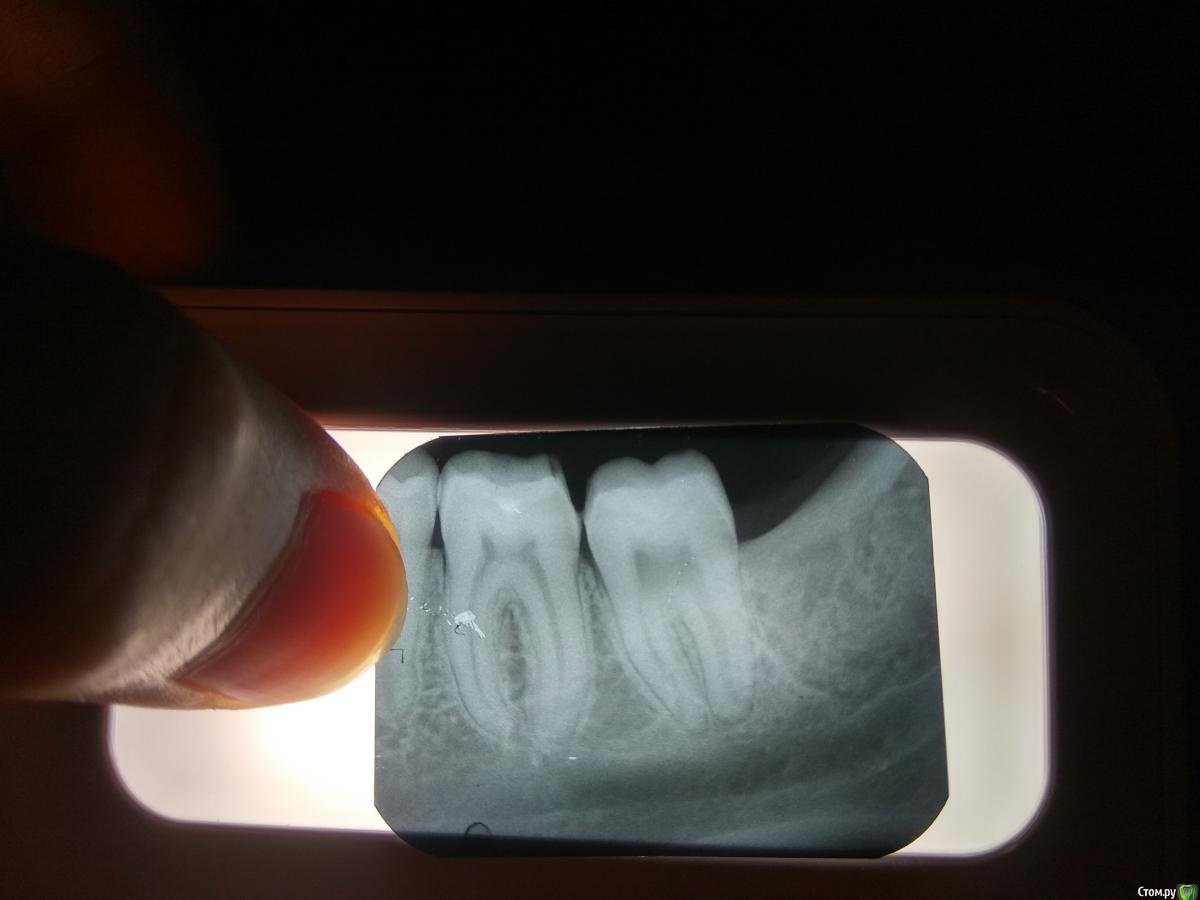

Начал болеть зуб, боль иногда уходит и потом снова появляется,на холодное и горячее реакции нету, а вот сладкое усиляет боль.Сходил к врачу, он ничего не увидел на 7 зубе(по ощущениям болит он), по панорамному снимку (2месячной давности)  врач заметил небольшой кариес между 6 и 7 зубом, после лечения боль осталась.Сходил сделал снимок,врачу который лечил еще не показывал. Действительно ли с зубом что-то не так или я сам себя накручиваю.